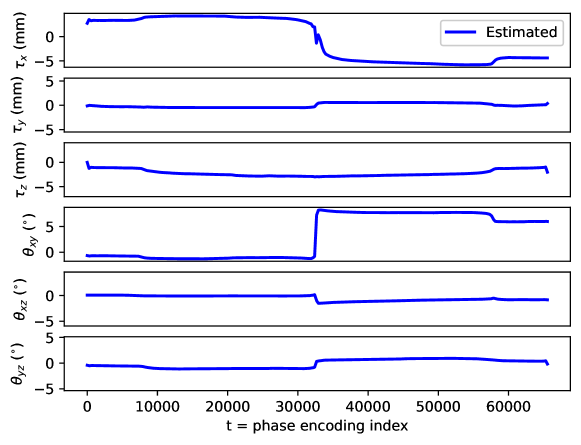

Appendix C Motion parameter estimation

The proposed motion correction algorithm described in Section 2 estimates the rigid motion that the object of interest undergoes during the scan, in order to undo its effect on the reconstructed 3D image. In 3D, the rigid motion is performed by: a plane rotation in the corresponding plane , a plane rotation in the plane, a plane rotation in the plane, a translation in the direction, a translation in the direction, and a translation in the direction (in this order). We adopt the following convention: the direction corresponds to the left-right direction, to the posterior-anterior direction, and to the inferior-superior direction, the plane corresponds to the axial plane, to the coronal plane, and to the sagittal plane. Left/right, anterior/posterior, and inferior/superior are meant from the patient perspective. The orientation of the rotation planes is determined by the right-hand rule.

By design, the prospectively-induced motion for all the experiments detailed in Section 3 follows a step-wise behavior (each step corresponding to a change of pose). In this appendix, we gather the estimated rigid motion parameters for the results shown in Section 4, as a function of time. As noted in the main body of the paper, time is equated to the phase-encoding plane coordinate index, ordered by the corresponding acquisition ordering. We display the estimated motion parameters in Figure 19 (see Sections 3.1, 4.1, Figure 2), Figure 20 (see Sections 3.1, 4.1, Figure 4), Figure 21 (see Sections 3.1, 4.1, Figure 6), Figure 22 (see Sections 3.2, 4.2, Figure 10), Figure 23 (see Sections 3.3, 4.3, Figure 12), and Figure 24 (see Sections 3.3, 4.3, Figure 14).